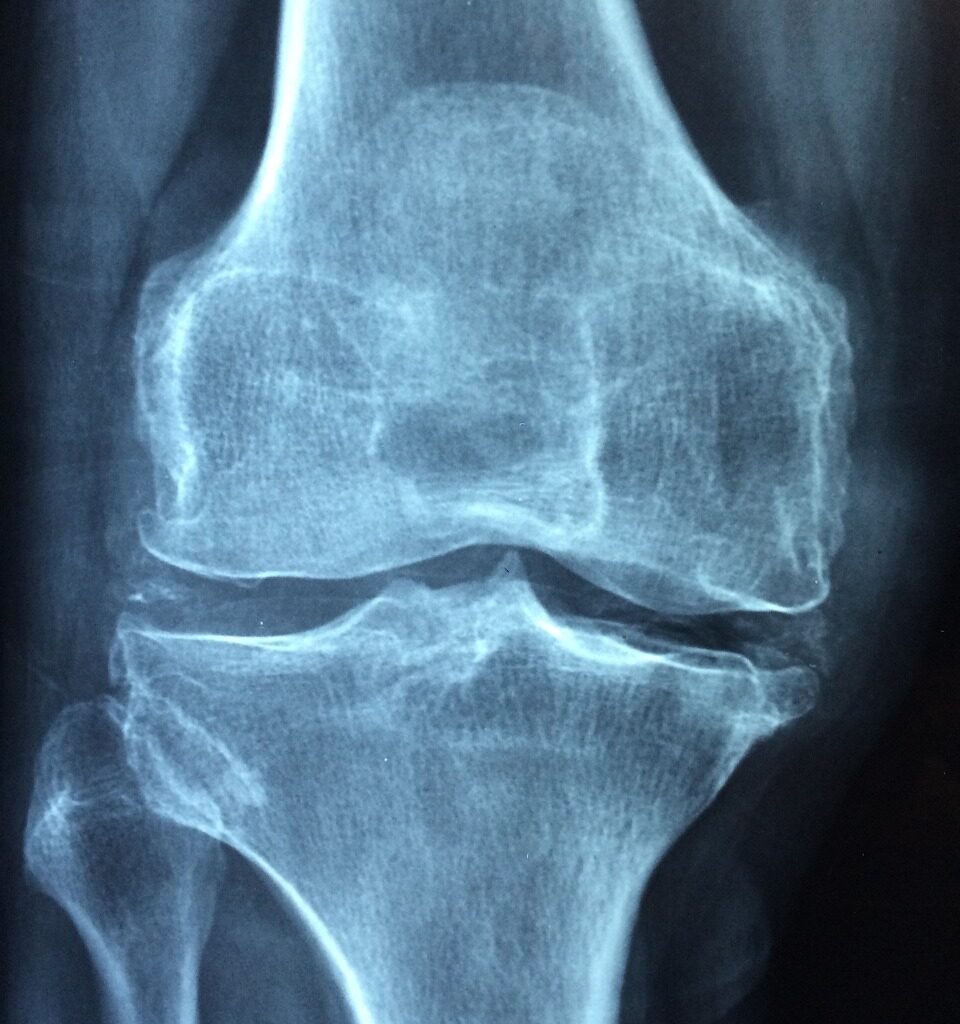

L’ostéoporose est une condition caractérisée par une faible densité osseuse, ce qui rend les os plus fragiles et plus susceptibles de se fracturer. La prévention de l’ostéoporose commence par des choix alimentaires judicieux, et un nutritionniste à Paris peut jouer un rôle clé dans ce processus.